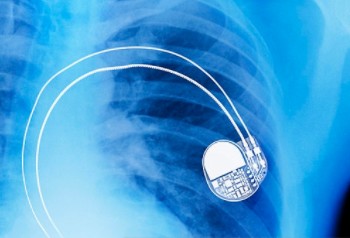

3月6日,武漢兒童醫院心血管內科團隊為笑笑實施手術。穿刺鎖骨下靜脈,將電極線放入心室,電池埋到皮下,火材盒大小的起搏器成功“埋伏”進笑笑體內。

張勇介紹,目前永久心臟起搏器植入術是治療不可逆的心臟高度傳導功能障礙的唯一安全有效方法,但兒童植入永久心臟起搏器并不常見,兒童心臟起搏器植入手術較成年人有很大的難度和不同,他解釋,體重越輕、年齡越小的患兒,起搏器囊袋越不容易做,電池越不容易裝進去。兒童會繼續生長發育,植入永久起搏器時需將電極線在心腔內打圈,在體內預留一定長度導線,以避免因身體長高而使導線牽拉。另外,兒童皮膚和皮下脂肪都很薄,起搏器作為金屬儀器有一定的重量,術后傷口往往因不能承力而非常容易破潰感染,術后要注意預防感染。